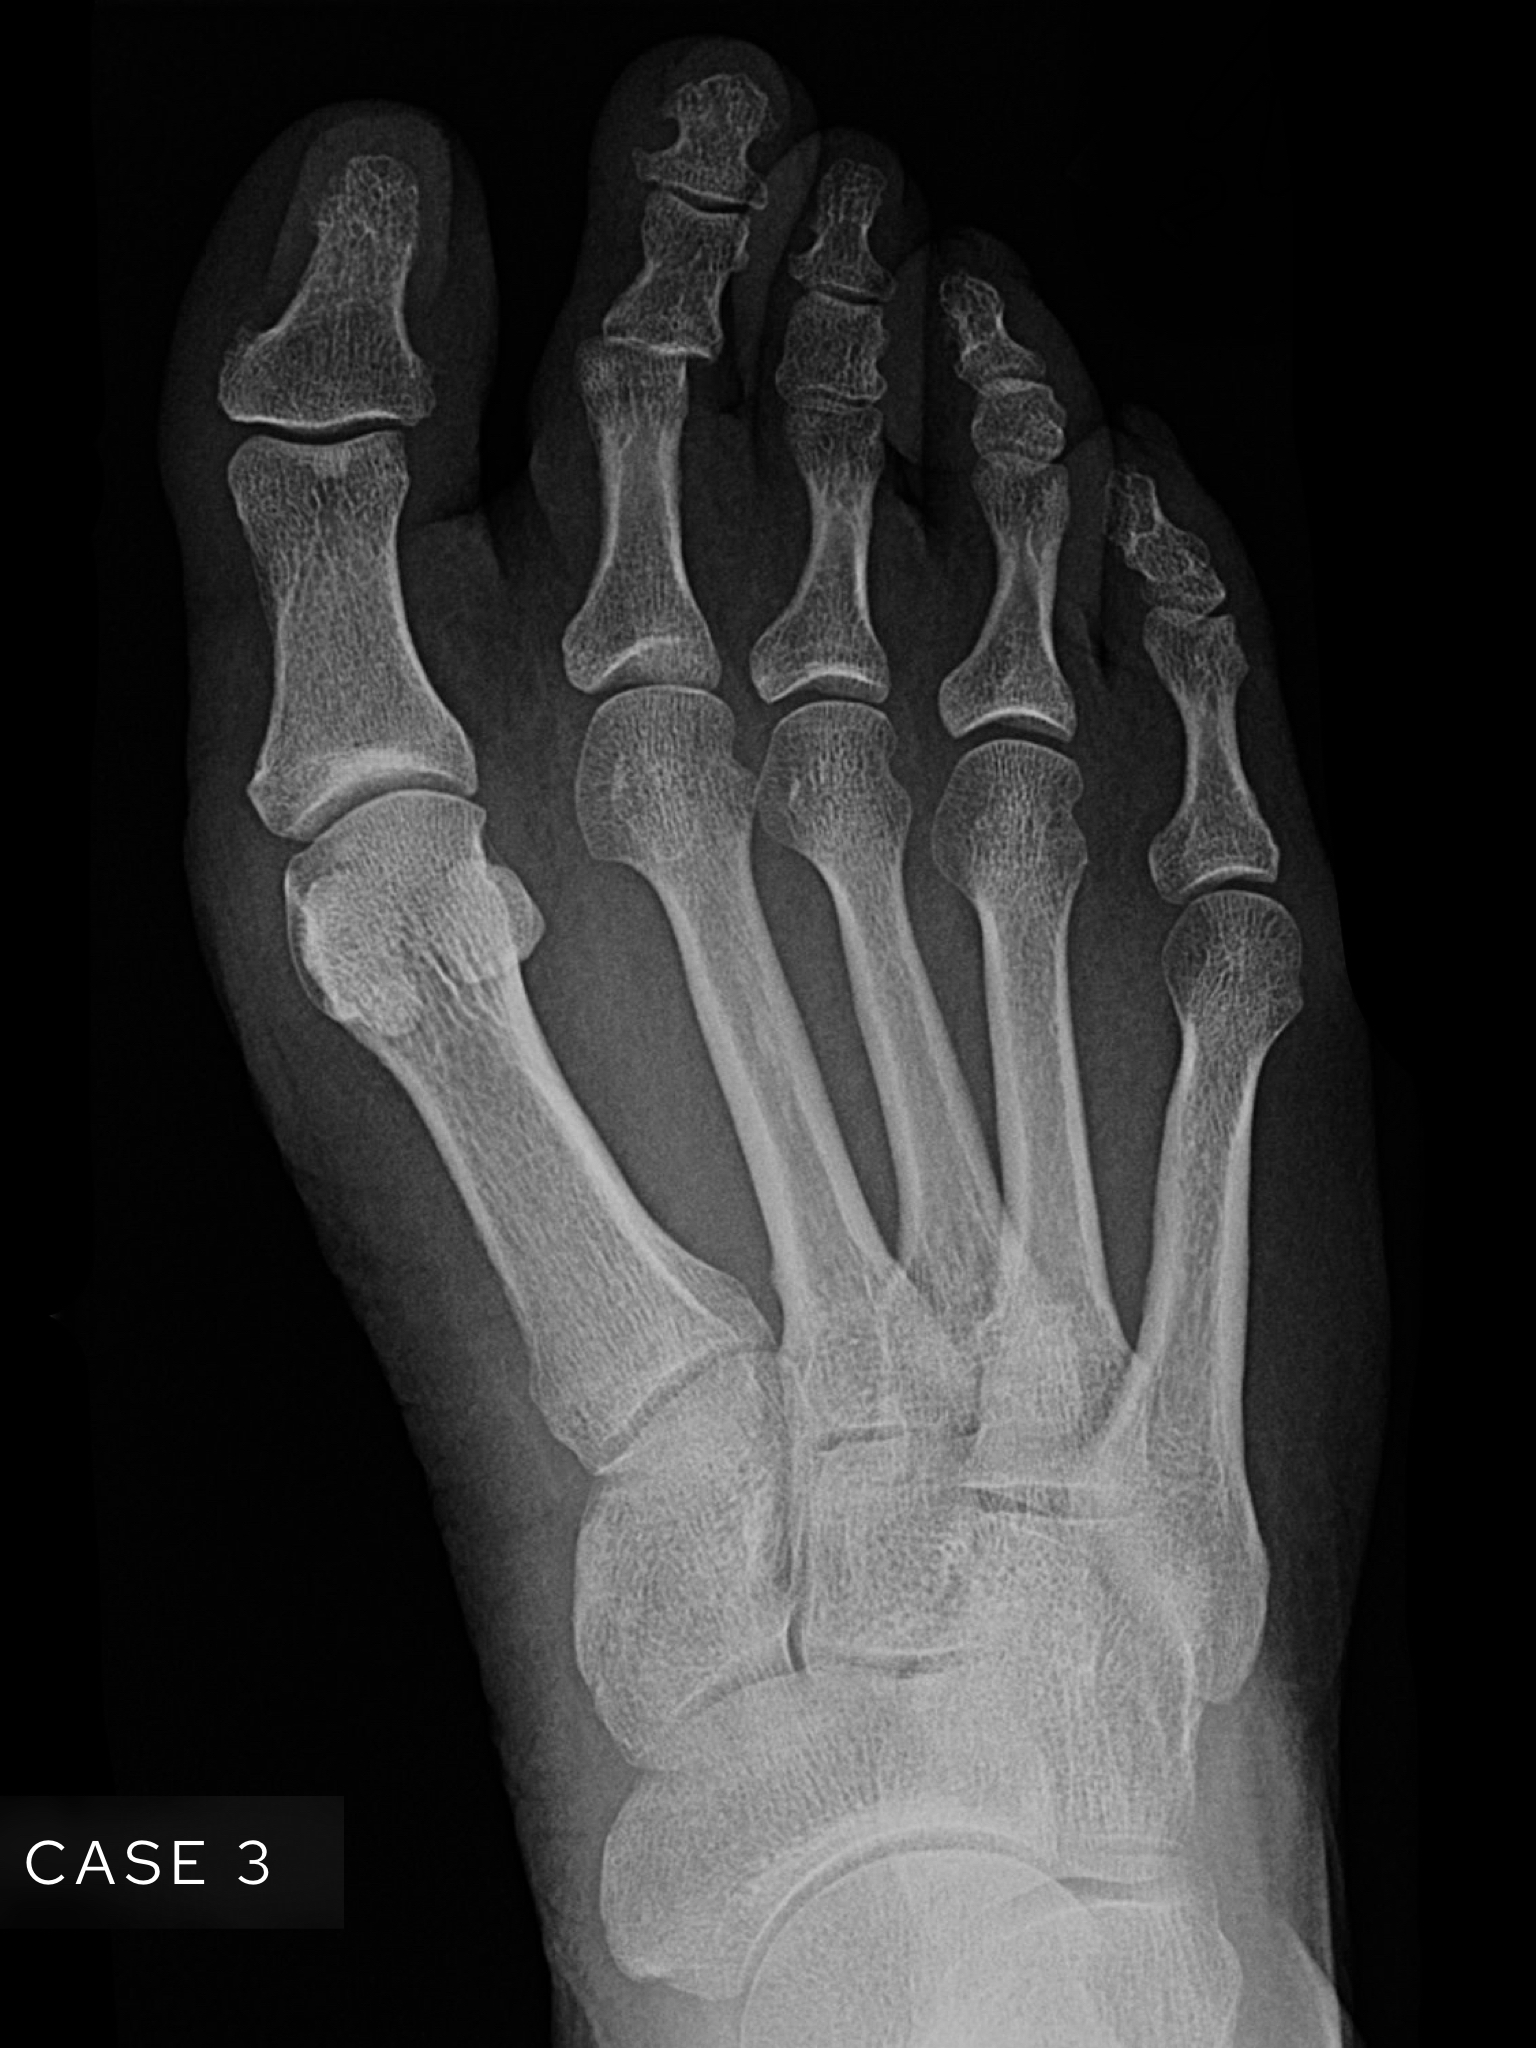

Case 3

A female in her 70s presents with foot pain after trauma. Have a look at her foot X-Ray below:

Choose from one of the following options: